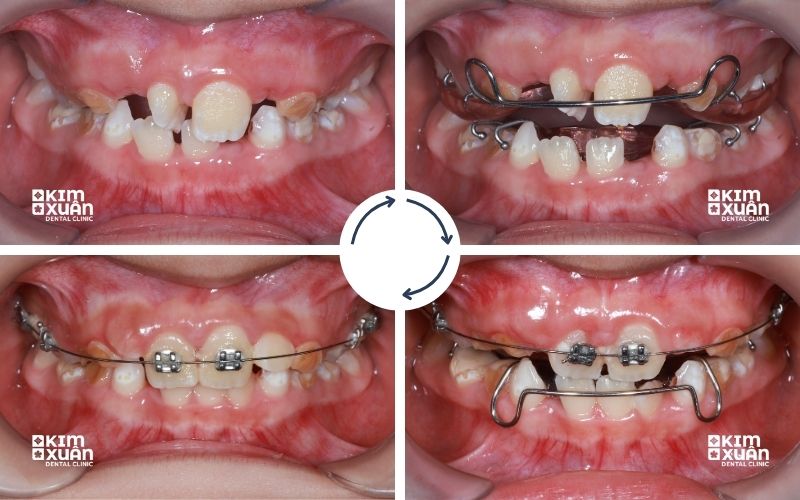

3.2. Niềng Răng Mắc Cài (Chỉ định trong trường hợp đặc biệt)

Niềng răng mắc cài thường không phải lựa chọn ưu tiên cho trẻ 8 tuổi, nhưng vẫn có thể được chỉ định trong một số trường hợp cần can thiệp sớm và kiểm soát lực kéo chính xác.

Thường áp dụng khi:

-

Sai lệch răng ở mức độ nặng (chen chúc nhiều, lệch khớp cắn rõ rệt)

-

Cần chỉnh một nhóm răng cụ thể với độ chính xác cao

-

Các phương pháp tháo lắp không mang lại hiệu quả mong muốn

Ưu điểm:

-

Tạo lực kéo ổn định, kiểm soát dịch chuyển răng tốt

-

Hiệu quả cao trong các ca phức tạp

Nhược điểm:

-

Khó vệ sinh răng miệng hơn, dễ đọng thức ăn

-

Trẻ có thể cảm thấy vướng víu, khó chịu trong thời gian đầu

-

Cần sự hợp tác tốt từ trẻ và theo dõi sát từ phụ huynh

Niềng răng mắc cài ở độ tuổi này cần được bác sĩ cân nhắc kỹ lưỡng để đảm bảo phù hợp với giai đoạn phát triển của trẻ, đồng thời tối ưu hiệu quả mà vẫn đảm bảo sự thoải mái trong sinh hoạt hàng ngày.